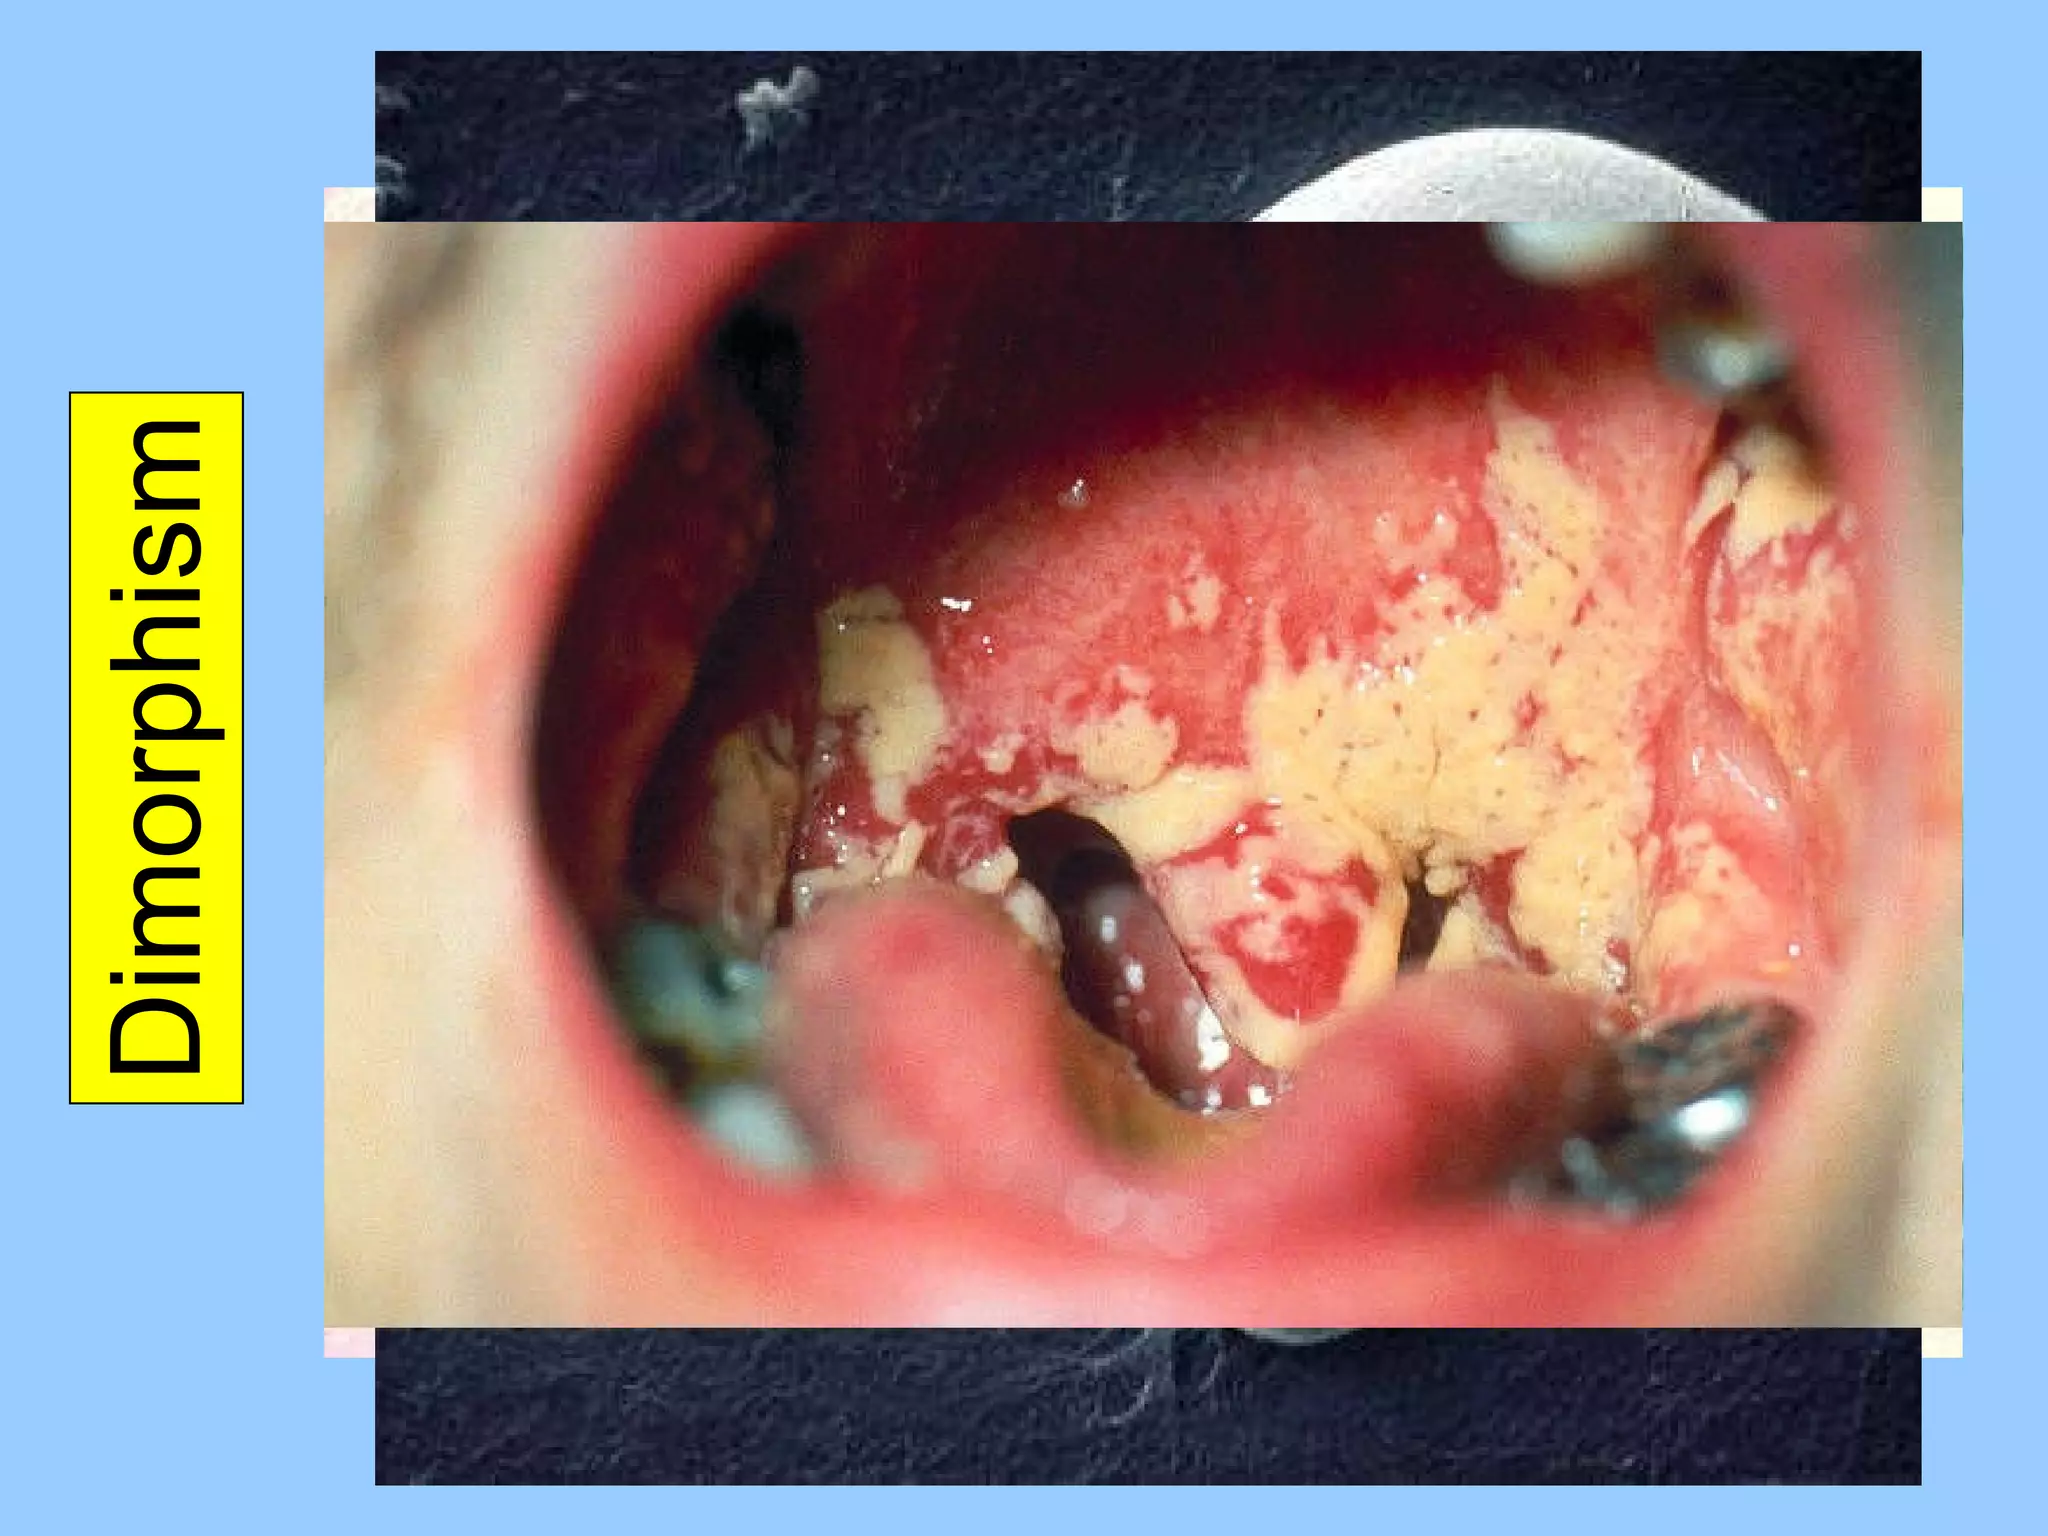

Dimorphism Some fungi can grow as yeasts or as hyphae, depending on growth conditions This can lead to a single fungal species being classified as more than one species Fungi also can display sexual versus asexual growth, further confusing fungal classification

Dimorphism Some fungican grow as yeasts or as hyphae, depending on growth conditions This can lead to a single fungal species being classified as more than one species Fungi also can display sexual versus asexual growth, further confusing fungal classification